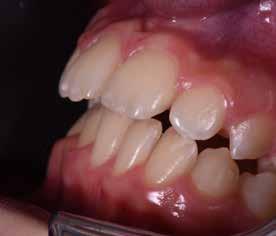

Presentazione del caso > F.V, bambino di cinque anni, presenta una malocclusione di II Classe scheletrica, III Classe dentale molare e canina destra e sinistra, morso inverso anteriore. Le arcate dentali mostrano usura degli elementi dentari anteriori a causa dell’occlusione patologica. Le linee mediane, superiore ed inferiore, sono centrate; il frenulo labiale superiore patologico per un’eccessiva estensione inter-incisale.

Dall’esame clinico si evince la III Classe dentale, l’inversione anteriore e l’over-jet negativo.

Una volta ottenuta la correzione del rapporto molare ed incisale, l’apparecchio elastodontico verrà portato dal paziente solo durante la notte per stabilizzare il risultato ottenuto e guidare l’eruzione degli elementi dentari per un totale di quattordici mesi di terapia. ad inizio trattamento :

Considerazioni > L’analisi cefalometrica ad inizio trattamento dimostra la II Classe scheletrica con protrusione del mascellare superiore e prognazia mandibolare; tendenza alla crescita verticale. L’esame clinico evidenzia una protrusione mandibolare funzionale.

55 54 ESTETICA FUNZIONE POSTURA Valori cefalometrici ad 1 anno di terapia : ANB ANB 3,8 Posizione del Mascellare SNA 91.40 Posizione della Mandibola SNB 87,60 Angolo Articolare SArGo 155,00 Angolo Goniaco ArGoMe 122,00 Angolo incisivo inf^Corpo madibolare IiMand 80,20 Angolo incisivo Sup^Base Cranica Ant. IsCran 111,05 Angolo Interincisivo II 138,00 72, 73 _ Over-bite e over-jet. 74 _ Immagine laterale destra. 75 _ Immagine laterale sinistra. Considerazioni > La terapia precoce di tali malocclusioni è di primaria importanza in quanto impedisce la formazione di malocclu-